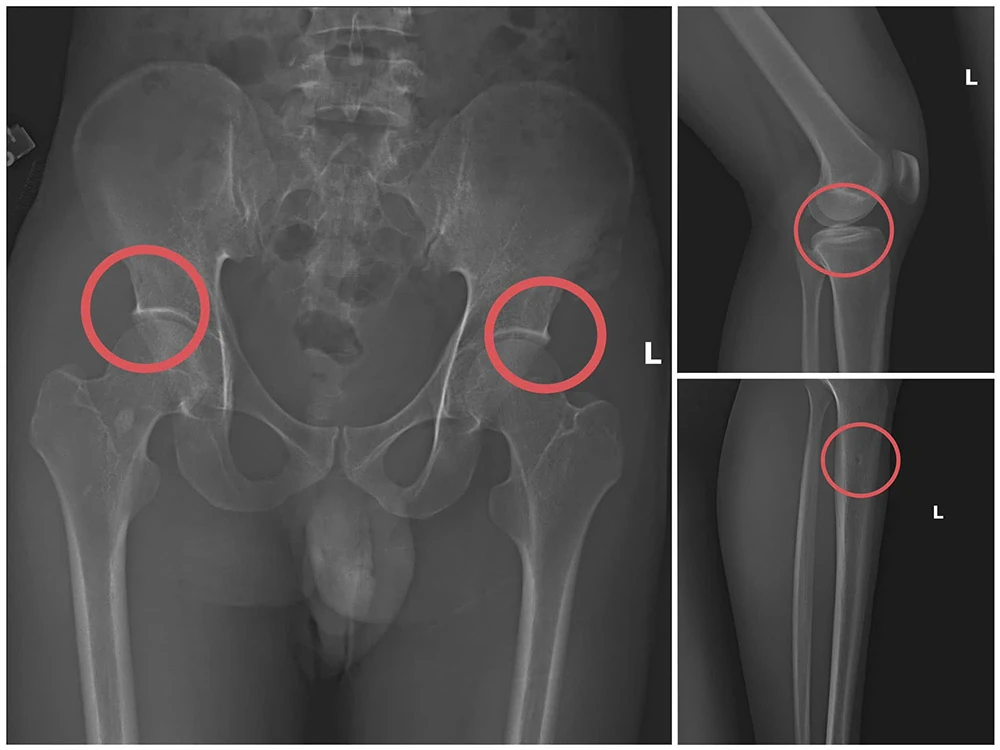

Bản phim chụp XQ một số tổn thương xương do đối tượng tạo ra

Đáng chú ý, Châu trực tiếp thực hiện hành vi tiêm thuốc mê rồi dùng kim tiêm, búa, đinh tác động vào xương người mua bảo hiểm, tạo nên các vết nứt, vỡ xương tương tự tai nạn thật. Khi thương tích đã tạo xong, Châu tiếp tục hướng dẫn các đối tượng dựng hiện trường giả như điện giật ngã, trượt chân ngã suối, nhằm hợp thức hóa bệnh án và hoàn thiện hồ sơ yêu cầu chi trả.

Thông qua các tài liệu thu thập được, Cơ quan Cảnh sát điều tra đã làm rõ đối tượng Tạ Minh Châu, sinh năm 1995, nguyên cán bộ Trung tâm Y tế huyện Cẩm Khê là kẻ chủ mưu, cầm đầu. Lợi dụng thời gian dài công tác trong ngành y và am hiểu sâu cấu tạo xương khớp, cũng như cơ chế chi trả bảo hiểm đối với các thương tích gãy xương có giá trị cao, Châu đã dựng lên một quy trình trục lợi bài bản, từ việc vận động mua bảo hiểm, tổ chức gây thương tích, đến hợp thức hóa hồ sơ bệnh án để chiếm đoạt tiền của các công ty bảo hiểm.

Theo đánh giá của đồng chí Giám đốc công an tỉnh, đây là thủ đoạn này vừa tàn nhẫn, vô nhân tính, coi thường sức khỏe, tính mạng của người tham gia, vừa được tính toán kỹ để gây thương tích đúng vị trí có mức chi trả cao, khiến các công ty bảo hiểm khó phát hiện dấu hiệu gian dối.